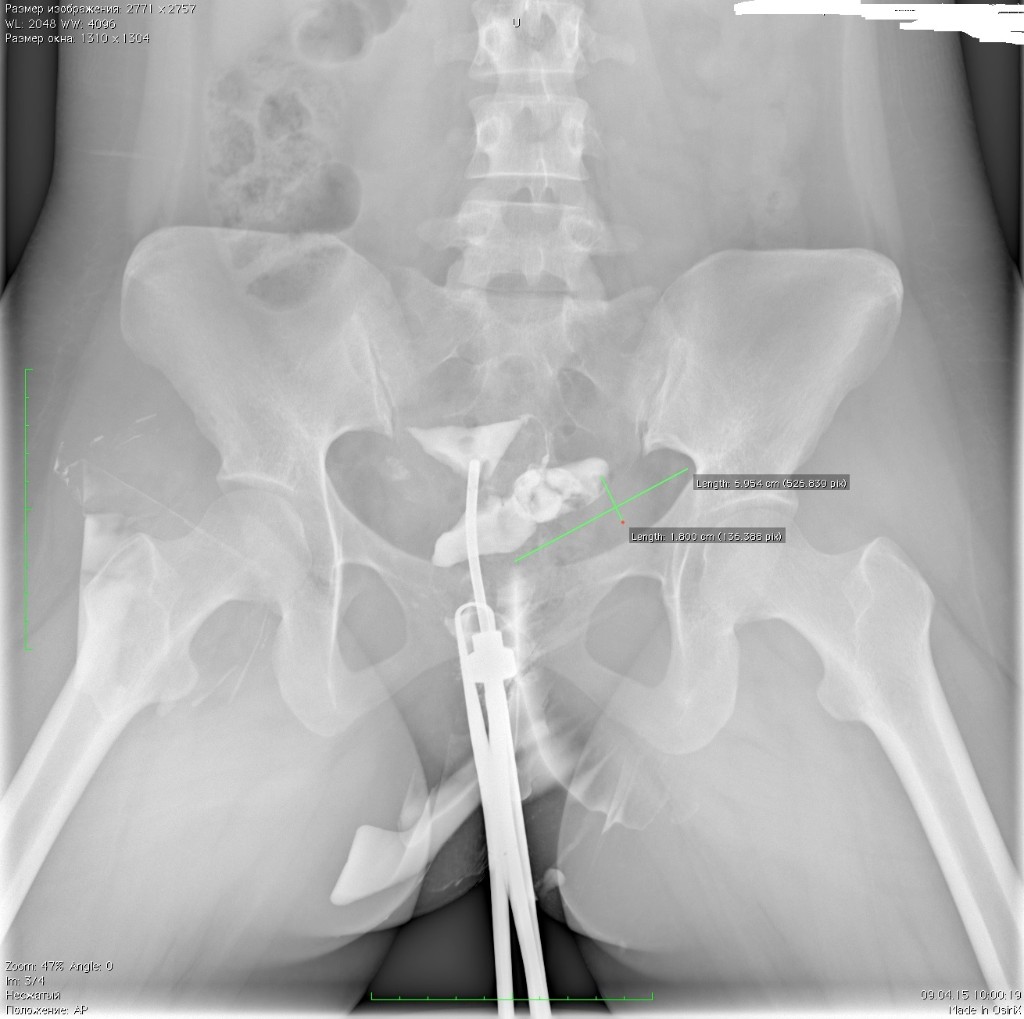

Гистеросальпингография: описание и фотографии